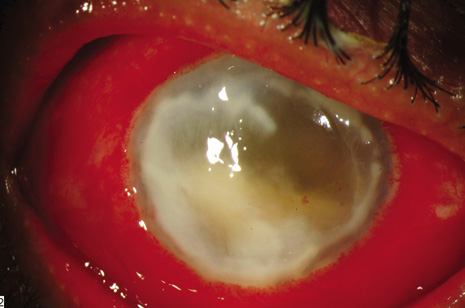

The diagnostic features of infectious endophthalmitis can be divided into two aspects: clinical recognition and microbiologic confirmation. The clinical signs of endophthalmitis vary depending on the preceding events or surgery, the infecting organism, the associated inflammation, and the duration of the disease. In acute-onset postoperative endophthalmitis, when bacteria are the etiologic agents, the hallmark of the clinical diagnosis is marked intraocular inflammation with hypopyon (Fig. 1).1,2 Other signs of acute-onset postoperative bacterial endophthalmitis include fibrin in the anterior chamber and on the intraocular lens, corneal edema, marked conjunctival congestion, lid edema, and vitritis. Retinal periphlebitis is another clinical sign that is diagnostically helpful in eyes with relatively clear media.35 Endophthalmitis caused by fungal organisms generally has less inflammation, a more indolent course, and less ocular pain. Endogenous candida cases often manifest as isolated white infiltrates in the formed vitreous overlying a focal area of chorioretinitis.24,35

Fig. 1. Acute-onset endophthalmitis following clear corneal cataract surgery. The patient shows conjunctival congestion, prominent fibrin in the pupil, and hypopyon.